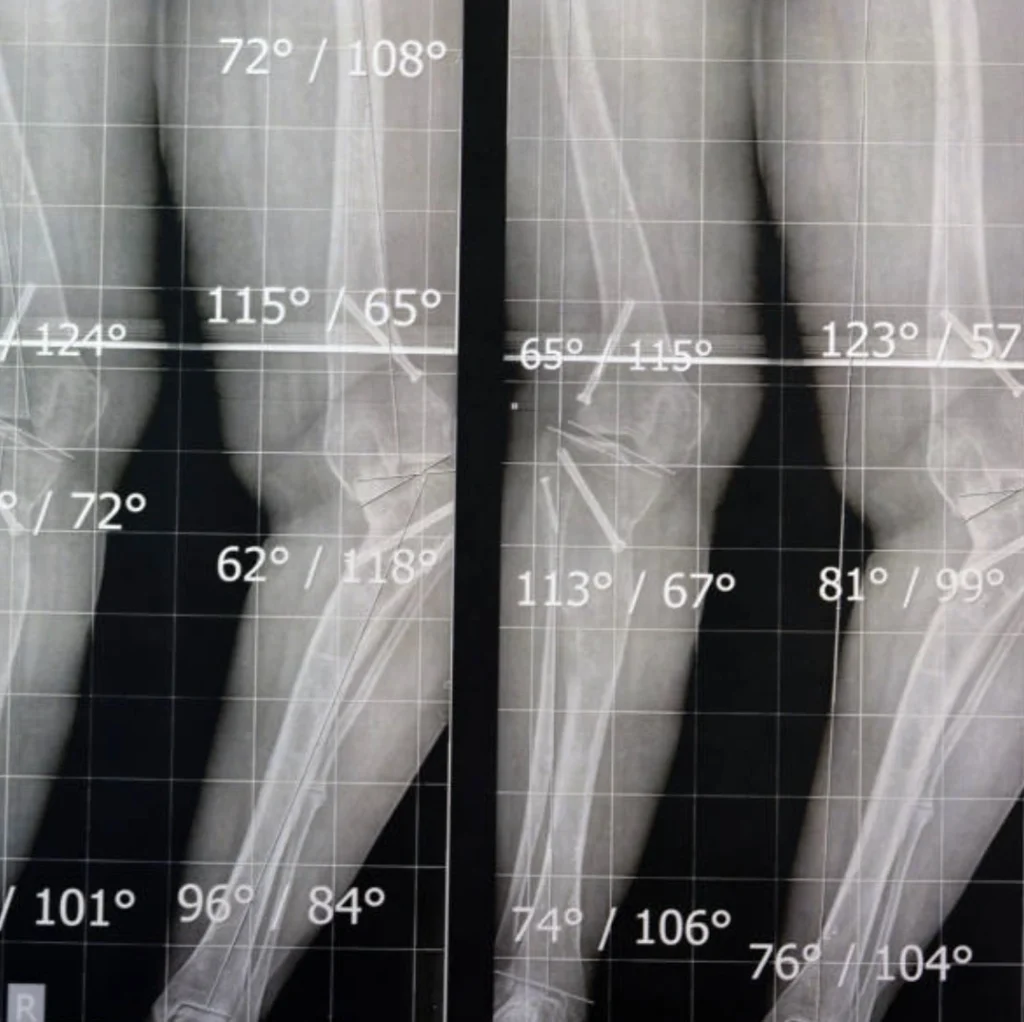

Comment Diagnostiquer un Œdème Osseux par IRM du Plateau Tibial ?

Le diagnostic repose sur des examens spécifiques :

- IRM (Imagerie par Résonance Magnétique) : Méthode de référence pour localiser et mesurer l’ampleur de l’œdème.

- Radiographies : Pour éliminer une fracture ou d’autres pathologies.

IRM de l'œdème osseux du plateau tibial : l'indispensable

Une IRM de l’œdème osseux est souvent incontournable pour un diagnostic précis. Il peut permettre de diagnostiquer un œdème osseux au pied, un œdème osseux à la cheville ou encore un œdème osseux au genou.